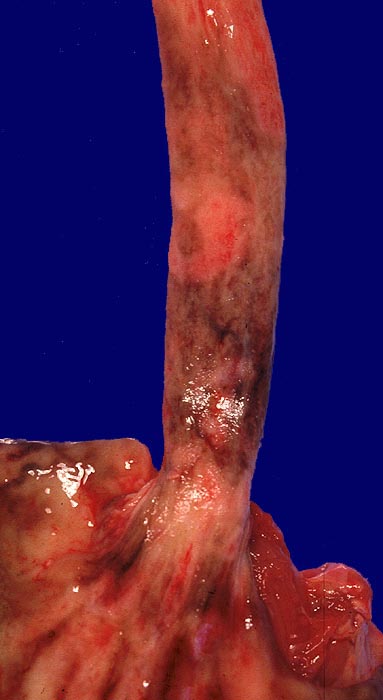

Endoskopisch finden sich abstreifbare weissgelbe krümelige Plaques, welche keine Prädilektionsstelle zeigen. Die Schleimhaut kann erodiert oder ulzeriert sein. In Klumpen von nekrotischen Plattenepithelzellen lassen sich mikroskopisch oft Sporen und Pseudohyphen nachweisen. Die Pseudohyphen wachsen oft senkrecht zur Epitheloberfläche. Besonders gut sichtbar werden die Pilze in der PAS oder Grocott Färbung. Zusätzlich besteht eine aktive Ösophagitis mit Infiltration der oberflächlichen Plattenepithelschicht durch neutrophile Granulozyten. Zahlreiche neutrophile Granulozyten in einem Ulkus weisen auf eine Soorösophagitis. Bei viral bedingten Ulzera (Herpes, CMV) prädominieren Makrophagen.

• Teils ulzerierte, teils erodierte Ösophagusmukosa.

Makroskopie